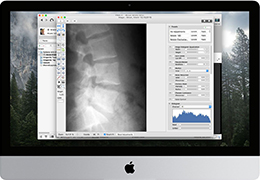

View X-Ray CT & MRI Scans Fast and Easily

Traditional multi-planar slicing

Multi-planar slicing.

Window/level (brightness and contrast) presets.